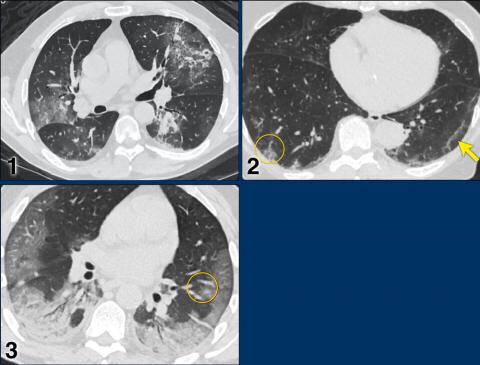

CO-RADS 5

CORADS 5

Case 1

Multifocal GGO and consolidation

Case 2

10 days of complaints.

CT: bilateral multifocal GGO, vascular thickening (circle), subpleural bands (arrow).

PCR: positive

Case 3

Eleven days of complaints

CT findings: Bilateral GGO and consilidation, basal preference, vascular thickening (circle).

Case 4

CT findings: multifocal areas of groundglass and consolidation

Case 5